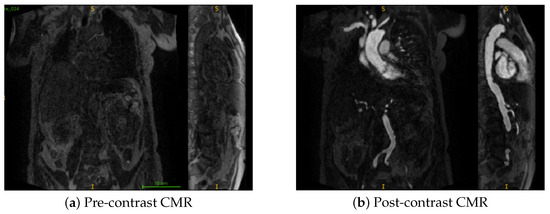

- Using a dataset of paired pre- and post-contrast scans, a modality ablation study is performed to systematically evaluate the distinct and combined contributions of each imaging modality. To the best of authors’ knowledge, this is the first such evaluation in the context of CMR-based TAVI planning.

3.3. Multimodal Ablation Study

4.3. Multimodal Ablation

- Impact of modality and pseudo-labels: The multimodal ablation study (Table 2) revealed post-contrast CMR as the most reliable input, delivering the highest Dice and lowest MAPE. By contrast, the inclusion of inferred cases slightly degraded performance, underscoring the sensitivity of segmentation models to label noise when pseudo-label confidence is not tightly controlled. The success of uncertainty-guided pseudo-labelling during active learning contrasted with blind inference performance, emphasizing that pseudo-labelling strategies require carefully designed confidence thresholds and quality control mechanisms.

- Model architecture vs. data quality: Differences between 3D U-Net and UMamba were modest compared to the impact of input modality. This suggests that improving data quality and curation may be more beneficial than pursuing marginal network refinements for this application. Surprisingly, combined pre- and post-contrast data did not consistently improve performance, suggesting current architectures may struggle with effective multimodal feature fusion or that alignment issues introduce artifacts.

- Limitations: The study was based on single-center data, which may limit generalizability across populations, scanner vendors, or imaging protocols. Performance on pre-contrast CMR remained substantially weaker, even when combined with post-contrast data, indicating that multimodal integration strategies require further refinement. Finally, as the pipeline is sequential, segmentation inaccuracies propagate to downstream diameter estimation, representing an area for future methodological improvement.